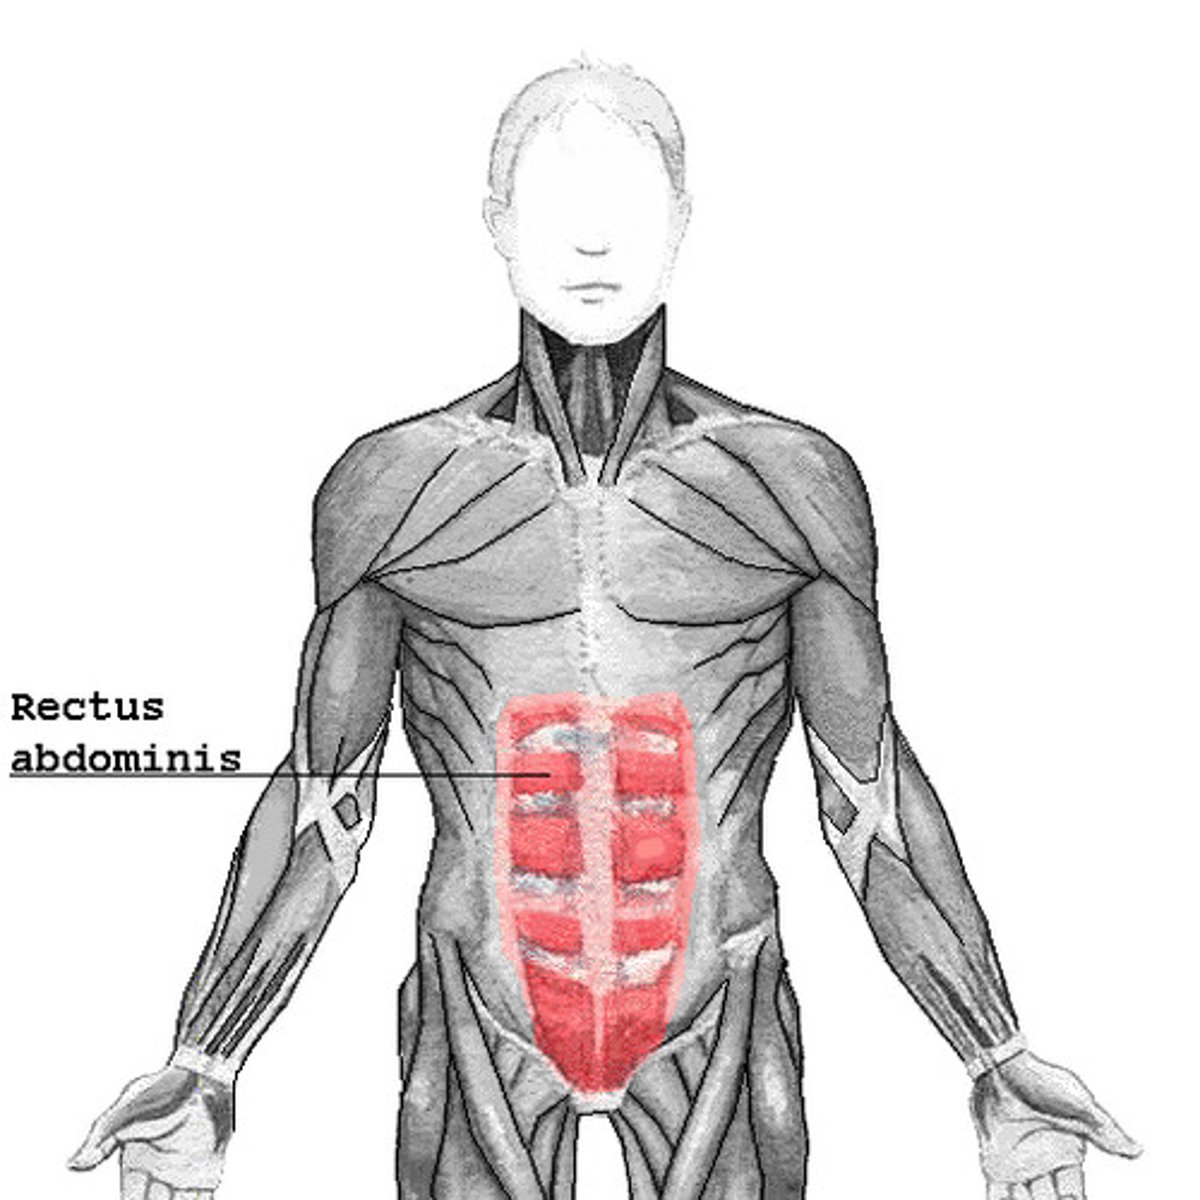

Rectus abdominis muscle extends from the ___ and ___ down to the ___

6th rib; xiphoid; pubis symphysis